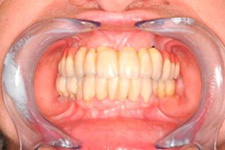

Implantáty jsou osvědčeným a vyzkoušeným řešením, které dnes umožňuje zhotovení estetické a funkční náhrady.

• Dokonalé obnovení funkce a estetiky

S pomocí zubních implantátů můžeme díky různým kotevním systémům (třmeny, kulové hlavy, Locatory) zajistit stabilitu a držení protézy nebo při použití většího počtu implantátů zhotovit pevné náhrady – můstky nalepené nebo našroubované na pevno na implantáty.

S těmito typy náhrad můžeme dosáhnout perfektní funkci, výbornou estetiku, fonetiku a současně zajistit u pacienta možnost dobré hygienickou péče a čištění, která je pro životnost implantátů velice důležitá.